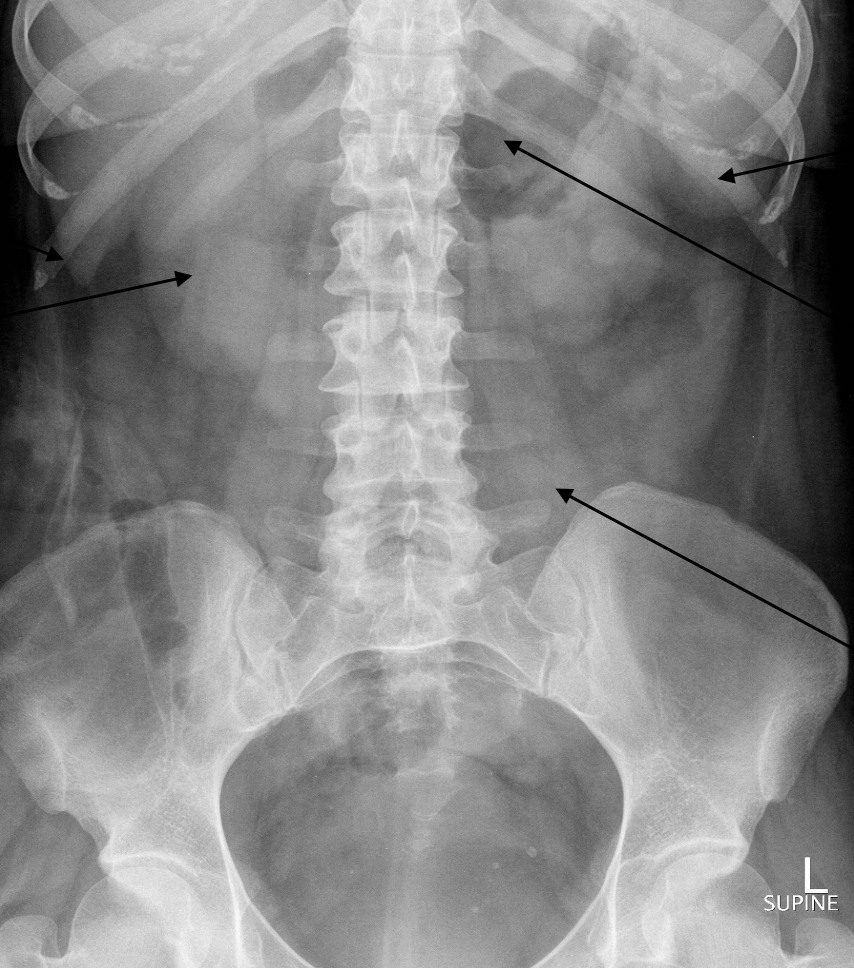

Label the structures

Top → large bowel

Middle → small bowel

Bottom → bladder